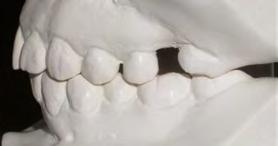

52 | SONRIENDO AL FUTURO

Tratamiento ortodóncico en paciente adulto tratado con extracciones de primeros molares permanentes. Reporte de caso

en paciente adulto tratado con extracciones de primeros molares permanentes. Reporte de caso